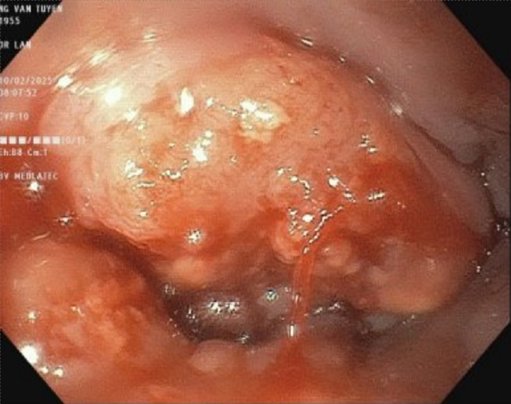

Đến Bệnh viện Đa khoa MEDLATEC thăm khám với tình trạng nuốt nghẹn, ăn uống nghẹn, sặc thức ăn lỏng, ợ hơi, ợ chua, người đàn ông 70 tuổi phát hiện ung thư thực quản nghi ngờ di căn phổi. Đặc biệt, trước đây 10 năm ông đã từng phải phẫu thuật cắt 3/4 dạ dày vì ung thư.